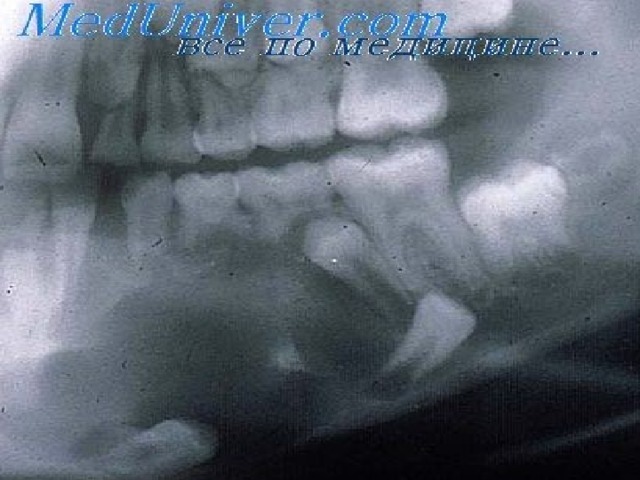

Одонтома нижней челюсти: фотографии и медицинская информация

Раздел: Фотобанк решений